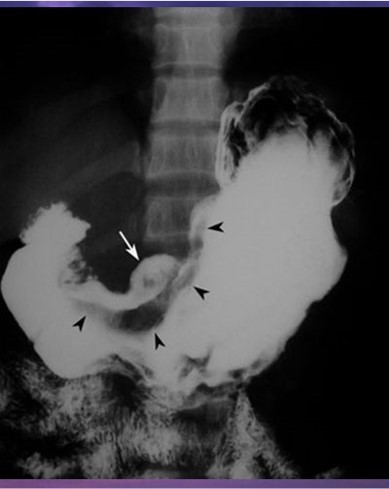

Crohn’s

Multiple aphthous (superficial) erosions are present on the antrum. Duodenal folds are thick and nodular (cobblestone mucosa).